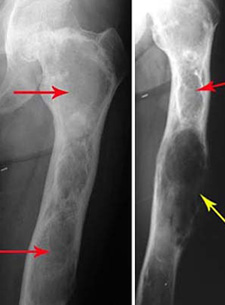

Abnormal condition

Abnormal condition 85 фото